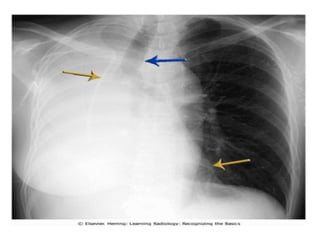

RLL collapse

• 3)

• Depression of horizontal fissure

• Increase opacity of collapse lower lobe

• In case of complete collapse of lower lobe it may

be so small that it merges with mediastinum and

produce a thin wedge shape shadow.

• Mediastinal parts and adjacent diaphragm

obscured

• Hila depressed

• Diaphragm elevation is not usual